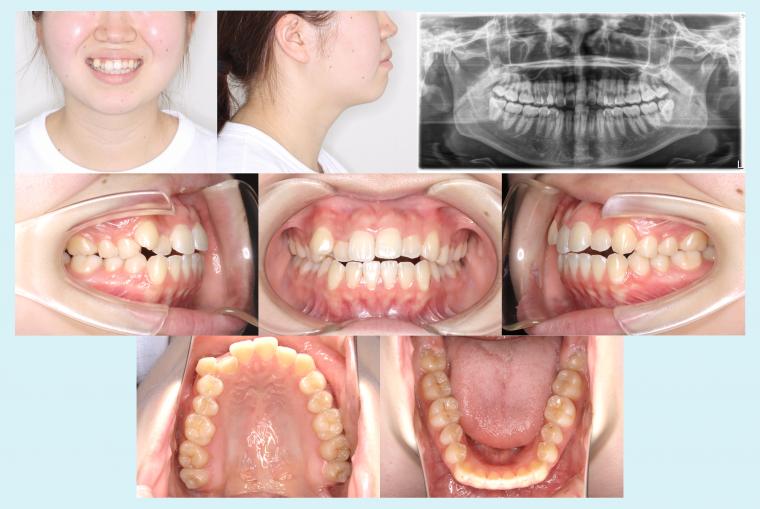

♯48 八重歯を治療した症例